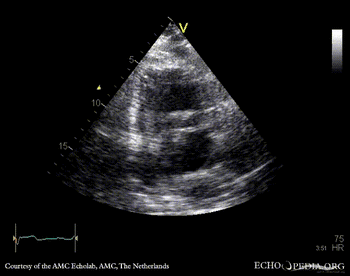

Aortic dissection type A

PLAX: dilated aortic root, dissection flap in ascending aorta PLAX: diameter of aortic root